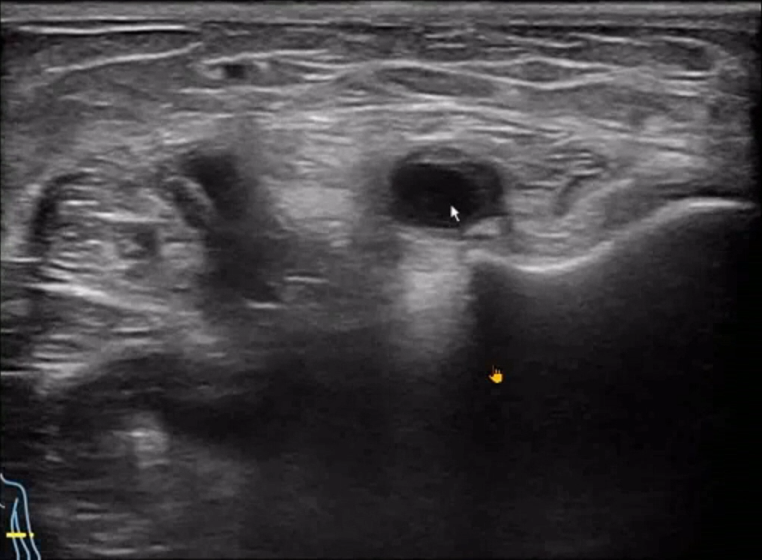

The handheld ultrasound machine indicated ulnar nerve compression in the right upper limb, likely due to synovial proliferation within the cubital tunnel and an external nerve sheath cyst in the forearm.

For healthcare professionals considering the purchase of a handheld ultrasound machine, cases like this underscore the importance of high-resolution imaging in diagnosing nerve compressions and related conditions.